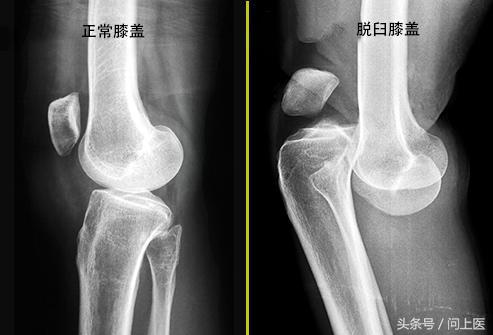

1. 脱位和骨折

如果撞击或摔倒严重损伤了膝盖,则可能会导致受损部位的骨骼(股骨、胫骨或膝盖骨)断裂或脱位,需要立即就诊。有时,骨折发生得较为缓慢,因为它会造成股骨末端出现微小裂缝,所以当患者开始使用膝盖时,才会发展为骨折。

为明确诊断,医生可能会进行膝盖X光或其他影像学检查。血液或膝盖里的液体样本有助于确认或排除某些疾病。治疗可能包括药物治疗、特殊锻炼、支架,或者在某些情况下手术。减肥有助于减轻膝盖受到的压力和张力。